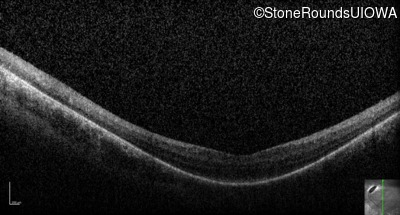

Optical Coherence Tomography - Right - 20/100 +1

Exemplar / OCT Stack

OCT Stack